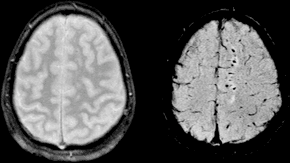

Diffuse axonal injury (DAI) is a brain injury in which scattered lesions occur over a widespread area in white matter tracts as well as grey matter. DAI is one of the most common and devastating types of traumatic brain injury and is a major cause of unconsciousness and persistent vegetative state after severe head trauma. It occurs in about half of all cases of severe head trauma and may be the primary damage that occurs in concussion. The outcome is frequently coma, with over 90% of patients with severe DAI never regaining consciousness. Those who awaken from the coma often remain significantly impaired. DAI can occur across the spectrum of traumatic brain injury (TBI) severity, wherein the burden of injury increases from mild to severe. Concussion may be a milder type of diffuse axonal injury. DAI is the result of traumatic shearing forces that occur when the head is rapidly accelerated or decelerated, as may occur in car accidents, falls, and assaults. Vehicle accidents are the most frequent cause of DAI; it can also occur as the result of child abuse such as in shaken baby syndrome. Immediate disconnection of axons may be observed in severe brain injury, but the major damage of DAI is delayed secondary axon disconnections, slowly developed over an extended time course. Tracts of axons, which appear white due to myelination, are referred to as white matter. Lesions in both grey and white matter are found in postmortem brains in CT and MRI exams. Besides mechanical breakage of the axonal cytoskeleton, DAI pathology also includes secondary physiological changes, such as interrupted axonal transport, progressive swellings known as axonal varicosities, and degeneration. Recent studies have linked these changes to twisting and misalignment of broken axon microtubules, as well as tau protein and amyloid precursor protein (APP) deposition. Lesions typically are found in the white matter of brains injured by DAI; these lesions vary in size from about 1–15 mm and are distributed in a characteristic pattern.